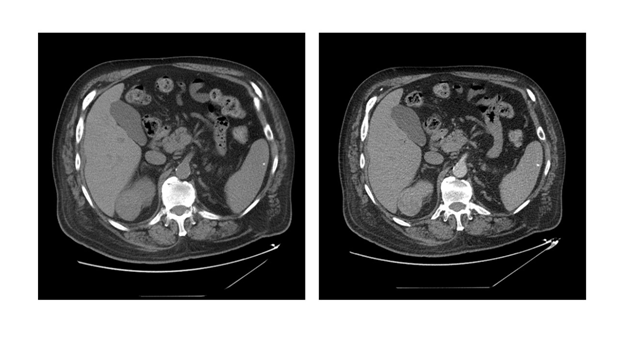

Figure 2 CT-scan Abdomen/pelvis, with/without IV contrast, 3 phases. Caudal Progression

Right: Non-contrast phase.

Left: Arterial phase, right upper pole, enhancing, posterior, close to collecting system, renal mass, 5.2 cm.